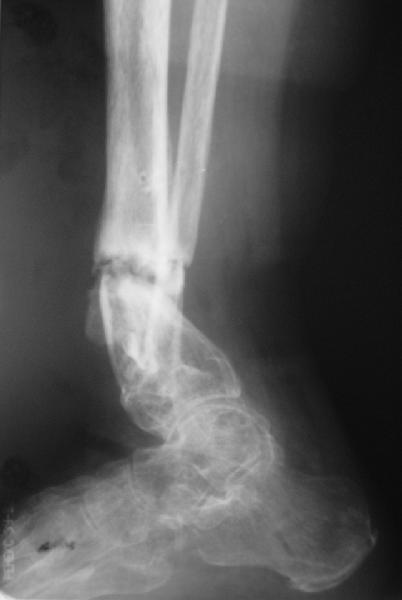

Глубокоуважаемые коллеги,Поступила женщина 72 лет. Полтора года назад - укушенная рана, перелом голени. Лечили аппаратом, не срослось. Долго не заживала рана.

Но вроде уже с полгода мягкие ткани закрыты. Спереди подпаянные рубцы. Есть приличная подвижность на уровне несращения. Картинки в приложении. Что предложите? Спсибо заранее.

Какова подвижность в голеностопе? Если движений в суставе практически нет (о чем можно предположить по Ргграмме) и инфекция исключена, я бы подумал о ретроградном штифтовании через таран.

Как ты думаешь, какова перспектива голеностопного сустава с такой исходной мобильностью? Судя по боковой проекции суставной хрящ в переднем отделе голеностопа разрушен, что при восстановлении оси голени и нагрузке приведет к ОА. Предвидеть в какой степени он будет выражен невозможно, вполне

Why the need for the Ilizarov if the nonunion is mobile? I would correct the deformity acutely with a fibular osteotomy if necessary to correct the

alignment and proceed with reamed IM nailing if there are no signs or history of infection. Minimum of 2 and preferably 3 distal locks, and put in a big enough nail to get a good isthmal fit. I reported a series of similar cases with an excellent success rate.

There are two fractures of the fibula. One the obvious one, and the second just above the syndesmosis. I would try to have a wire transfixing the lower tibial and fibular fragments.

Долго искал рентгенограммы. К сожалению без успеха. По Р гр примерно тоже самое что и на представленных снимках. В переломе полная подвижность. Голеностопный сустав "умер".